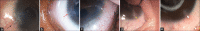

Results: Forty-one children (72 eyes) were included in the study, of which 31 children (62 eyes) underwent bilateral surgery while 10 (10 eyes) underwent unilateral surgery. Sixty-four nylon sutures were placed in 32 children (34 eyes), of which 22 (34.4%) were removed due to suture-related complications, whereas 14 (19.7%) (P = 0.03) of the 71 Vicryl sutures placed in 32 children (38 eyes) needed suture removal at an average of 2.9 weeks with the earliest at 6 days postoperatively. The odds of Vicryl suture being removed was 0.42 times with respect to nylon. The most common reason encountered for suture removal in both the materials was sutures becoming loose (16.3%), followed by vascularization (14.1%), infiltration (1.5%), and opacification (4.4%).

Figures